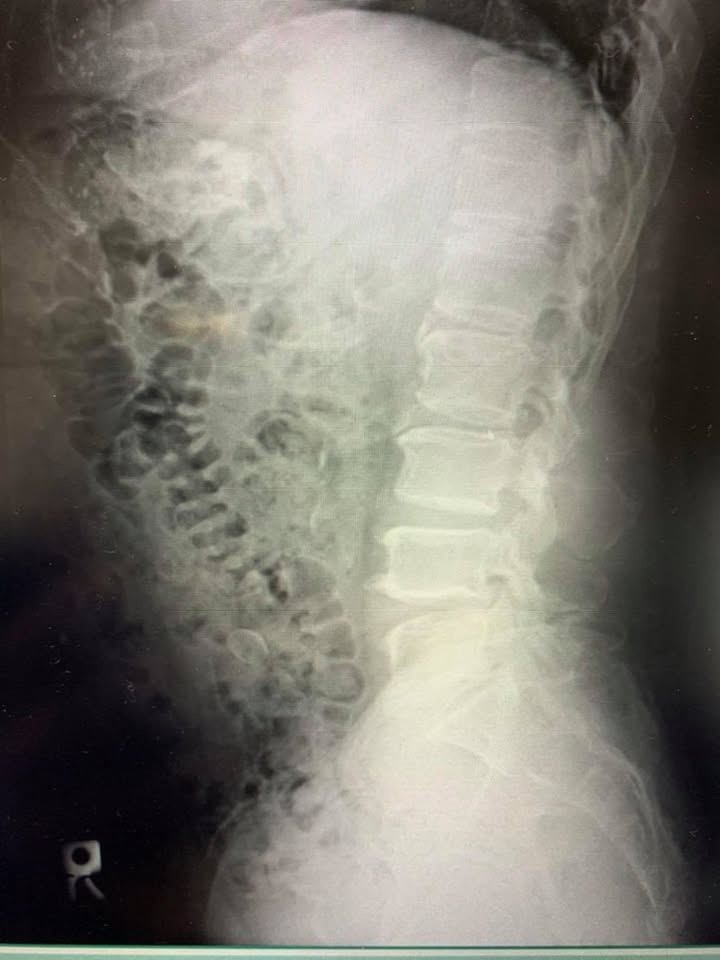

林阿伯今年摔倒後抱怨左邊腰痛連至小腿外側跟前測,疼痛的時間快四個多月,大醫院拍片檢查證實腰椎滑脫合併椎管狹窄,最近這四個月嚴重惡化!來診時候已經需要拐杖,他面露非常痛苦的表情,說大腿跟小腿被針扎的感覺非常痛苦,因為狀況其實蠻惡化的,所以按照慣例先治療四次,如果有改善就繼續治療下去,如果四次效果還是不好可能還是要去大醫院開刀

L4L5腰椎一級滑脫合併第五椎管狹窄